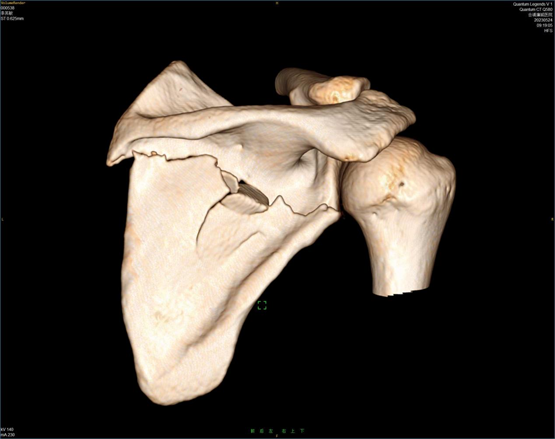

2.急诊以外伤为主:宽腾医疗CT系列采用大孔径设计,急诊外伤患者等特殊体位患者更大包容性,一站式急诊扫描流程,智能摆位,一键建档,最快0.5秒机架旋转,同台多平面重组/3D多序列多算法重建图像,为医生争取抢救黄金时间。

目前,通过对当地其他医院的CT和现已装机的64排128层螺旋CT图像质量进行对比分析发现,两者在扫描范围上有很大差异,这对于提高临床医生对疾病的认识和诊治水平有着十分重要的意义;另外,其相对于普通设备而言具有更大的体量优势和功能优势,使得它能够满足不同病人的需求。同时,对心脏成像、脑血管综合解决方案、血管成像、肺结节检查及结肠病变普查等多项科研技术实现了重大突破。